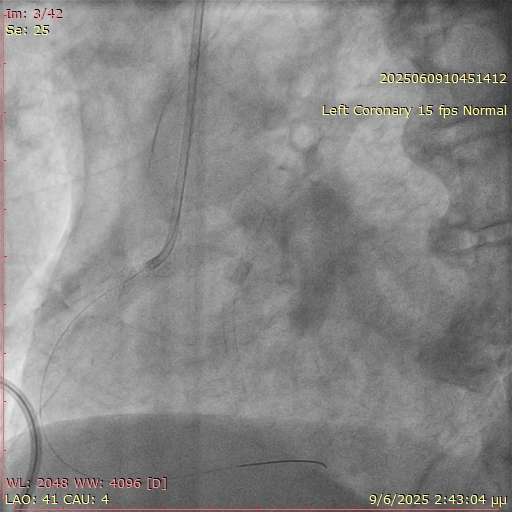

Unexpected resistance was encountered while attempting to deliver balloons across the ostial segment (Figure 2). Suspecting an underlying issue, the angiographic projection was modified to a more cranial view. This revealed that a significant portion of the prior stent was protruding into the aorta, obstructing device passage (Figure 3).